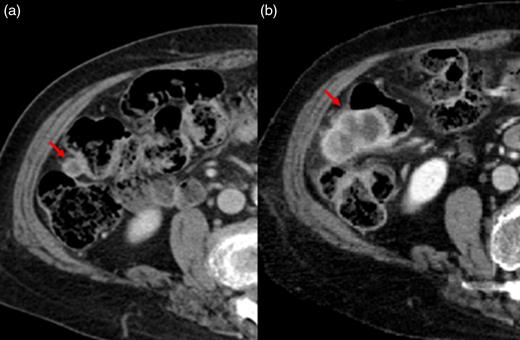

There was no evidence of tumor in the submandibular gland. Histological examination showed poorly differentiated SCC in the lymph nodes located at Level II (Fig. 1a). The patient was considered to have a carcinoma of unknown primary site because no primary lesions were found on detailed examinations of the esophagus, lung, uterine cervix and skin. A preoperative computed tomographic (CT) scan showed a small lesion with contrast effect in the transverse colon, which was difficult to distinguish from inflammation. Three months after operation, it was noted that the colonic lesion had grown considerably (Fig. 2). Fluorine-18 fluorodeoxyglucose positron emission tomography showed abnormal uptake in the transverse colon, but there was no accumulation at other sites (Fig. 3).

A preoperative CT scan showed a small lesion with contrast effect in the transverse colon, which was difficult to distinguish from inflammation (a). Three months after operation, it was noted that the colonic lesion had grown considerably (b).